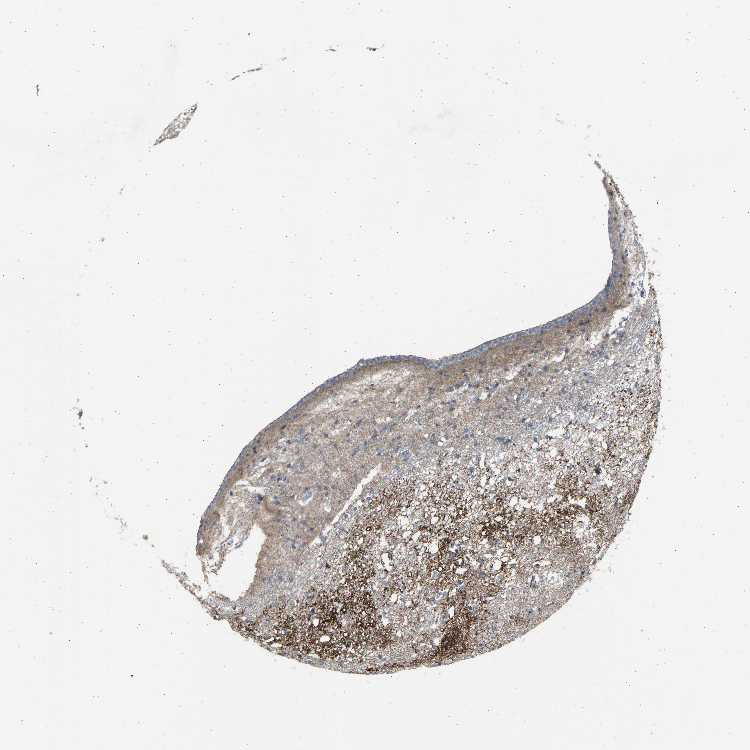

CAUDATE - Antibody stainingi

Antibody staining in the annotated cell types in the current human tissue is reported as not detected, low, medium, or high, based on conventional immunohistochemistry profiling in selected tissues. This score is based on the combination of the staining intensity and fraction of stained cells.

Each image is clickable and will lead to virtual microscopy that enables deeper exploration of all samples and also displays staining intensity scores, fraction scores and subcellular localization as well as patient and tissue information for each sample.

Antibody HPA020060

Glial cells Medium

Neuronal cells Medium